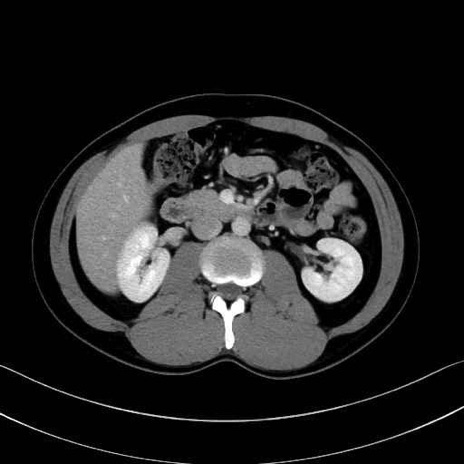

【症例】20歳代 男性 スクリーニング

脾動脈の画像解剖

■起始:典型的には腹腔動脈幹(celiac trunk)から左胃動脈・総肝動脈とともに三分岐し、脾動脈は左後上方へ向かう。

■走行:膵上縁または膵実質背側を蛇行しながら左方へ進み、膵尾部近傍で脾門へ至る。蛇行の程度は個体差が大きい。

■終枝:脾門部で複数の終末枝に分かれ、上極・下極枝や脾門枝群を形成する。胃短動脈群や左胃大網動脈はしばしば脾動脈から分岐する。